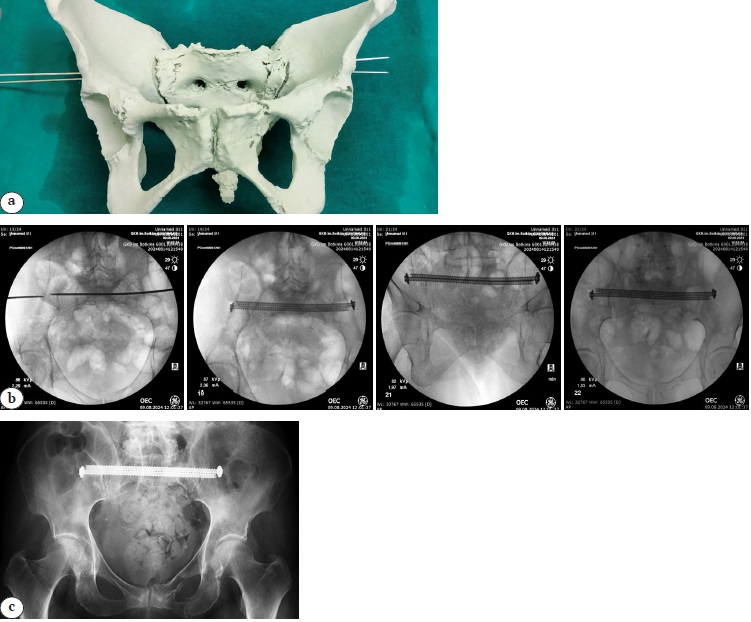

The physical 3D model was then sterilized using low-temperature plasma to allow intraoperative interaction with it (Figure 4).

Figure 4 (a). Process and result of using 3D model: a — model prepared for sterilization;

Figure 4 (b, c). Process and result of using the 3D model: b — radiographic control during surgery; c — postoperative X-ray